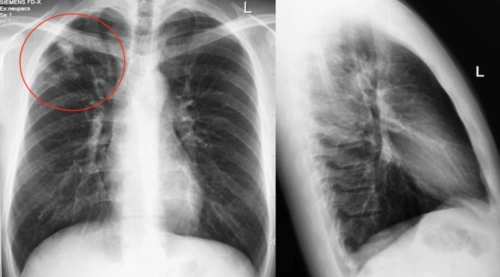

陈起航教授:肺结核的影像学评价——遏制,终止,终结肺结核(2)_腾讯